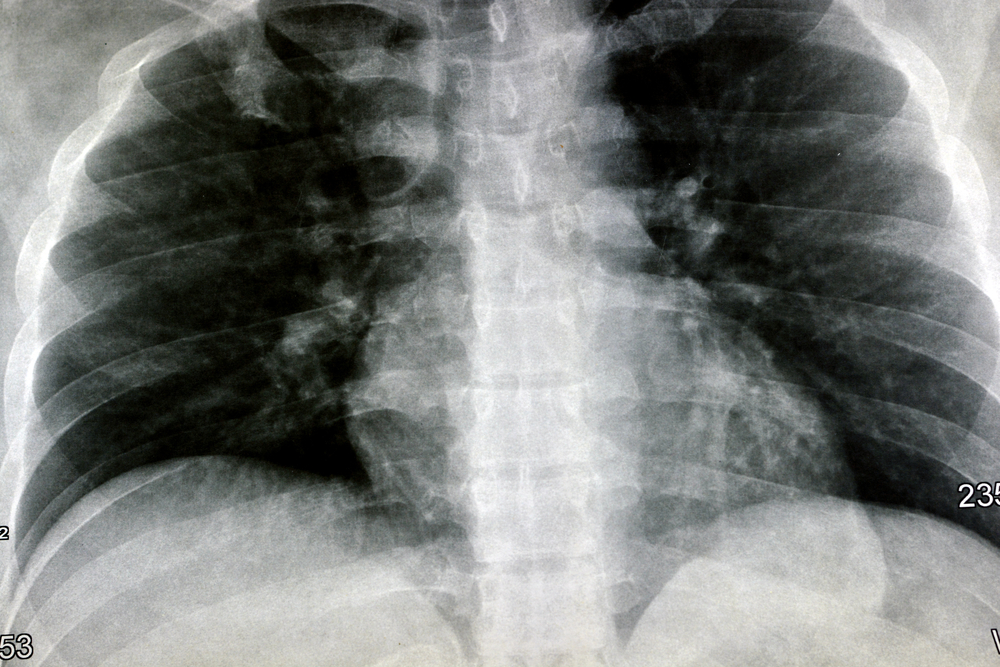

| ◘ | Bronkitis bisa berkembang menjadi pneumonia radang paru. |